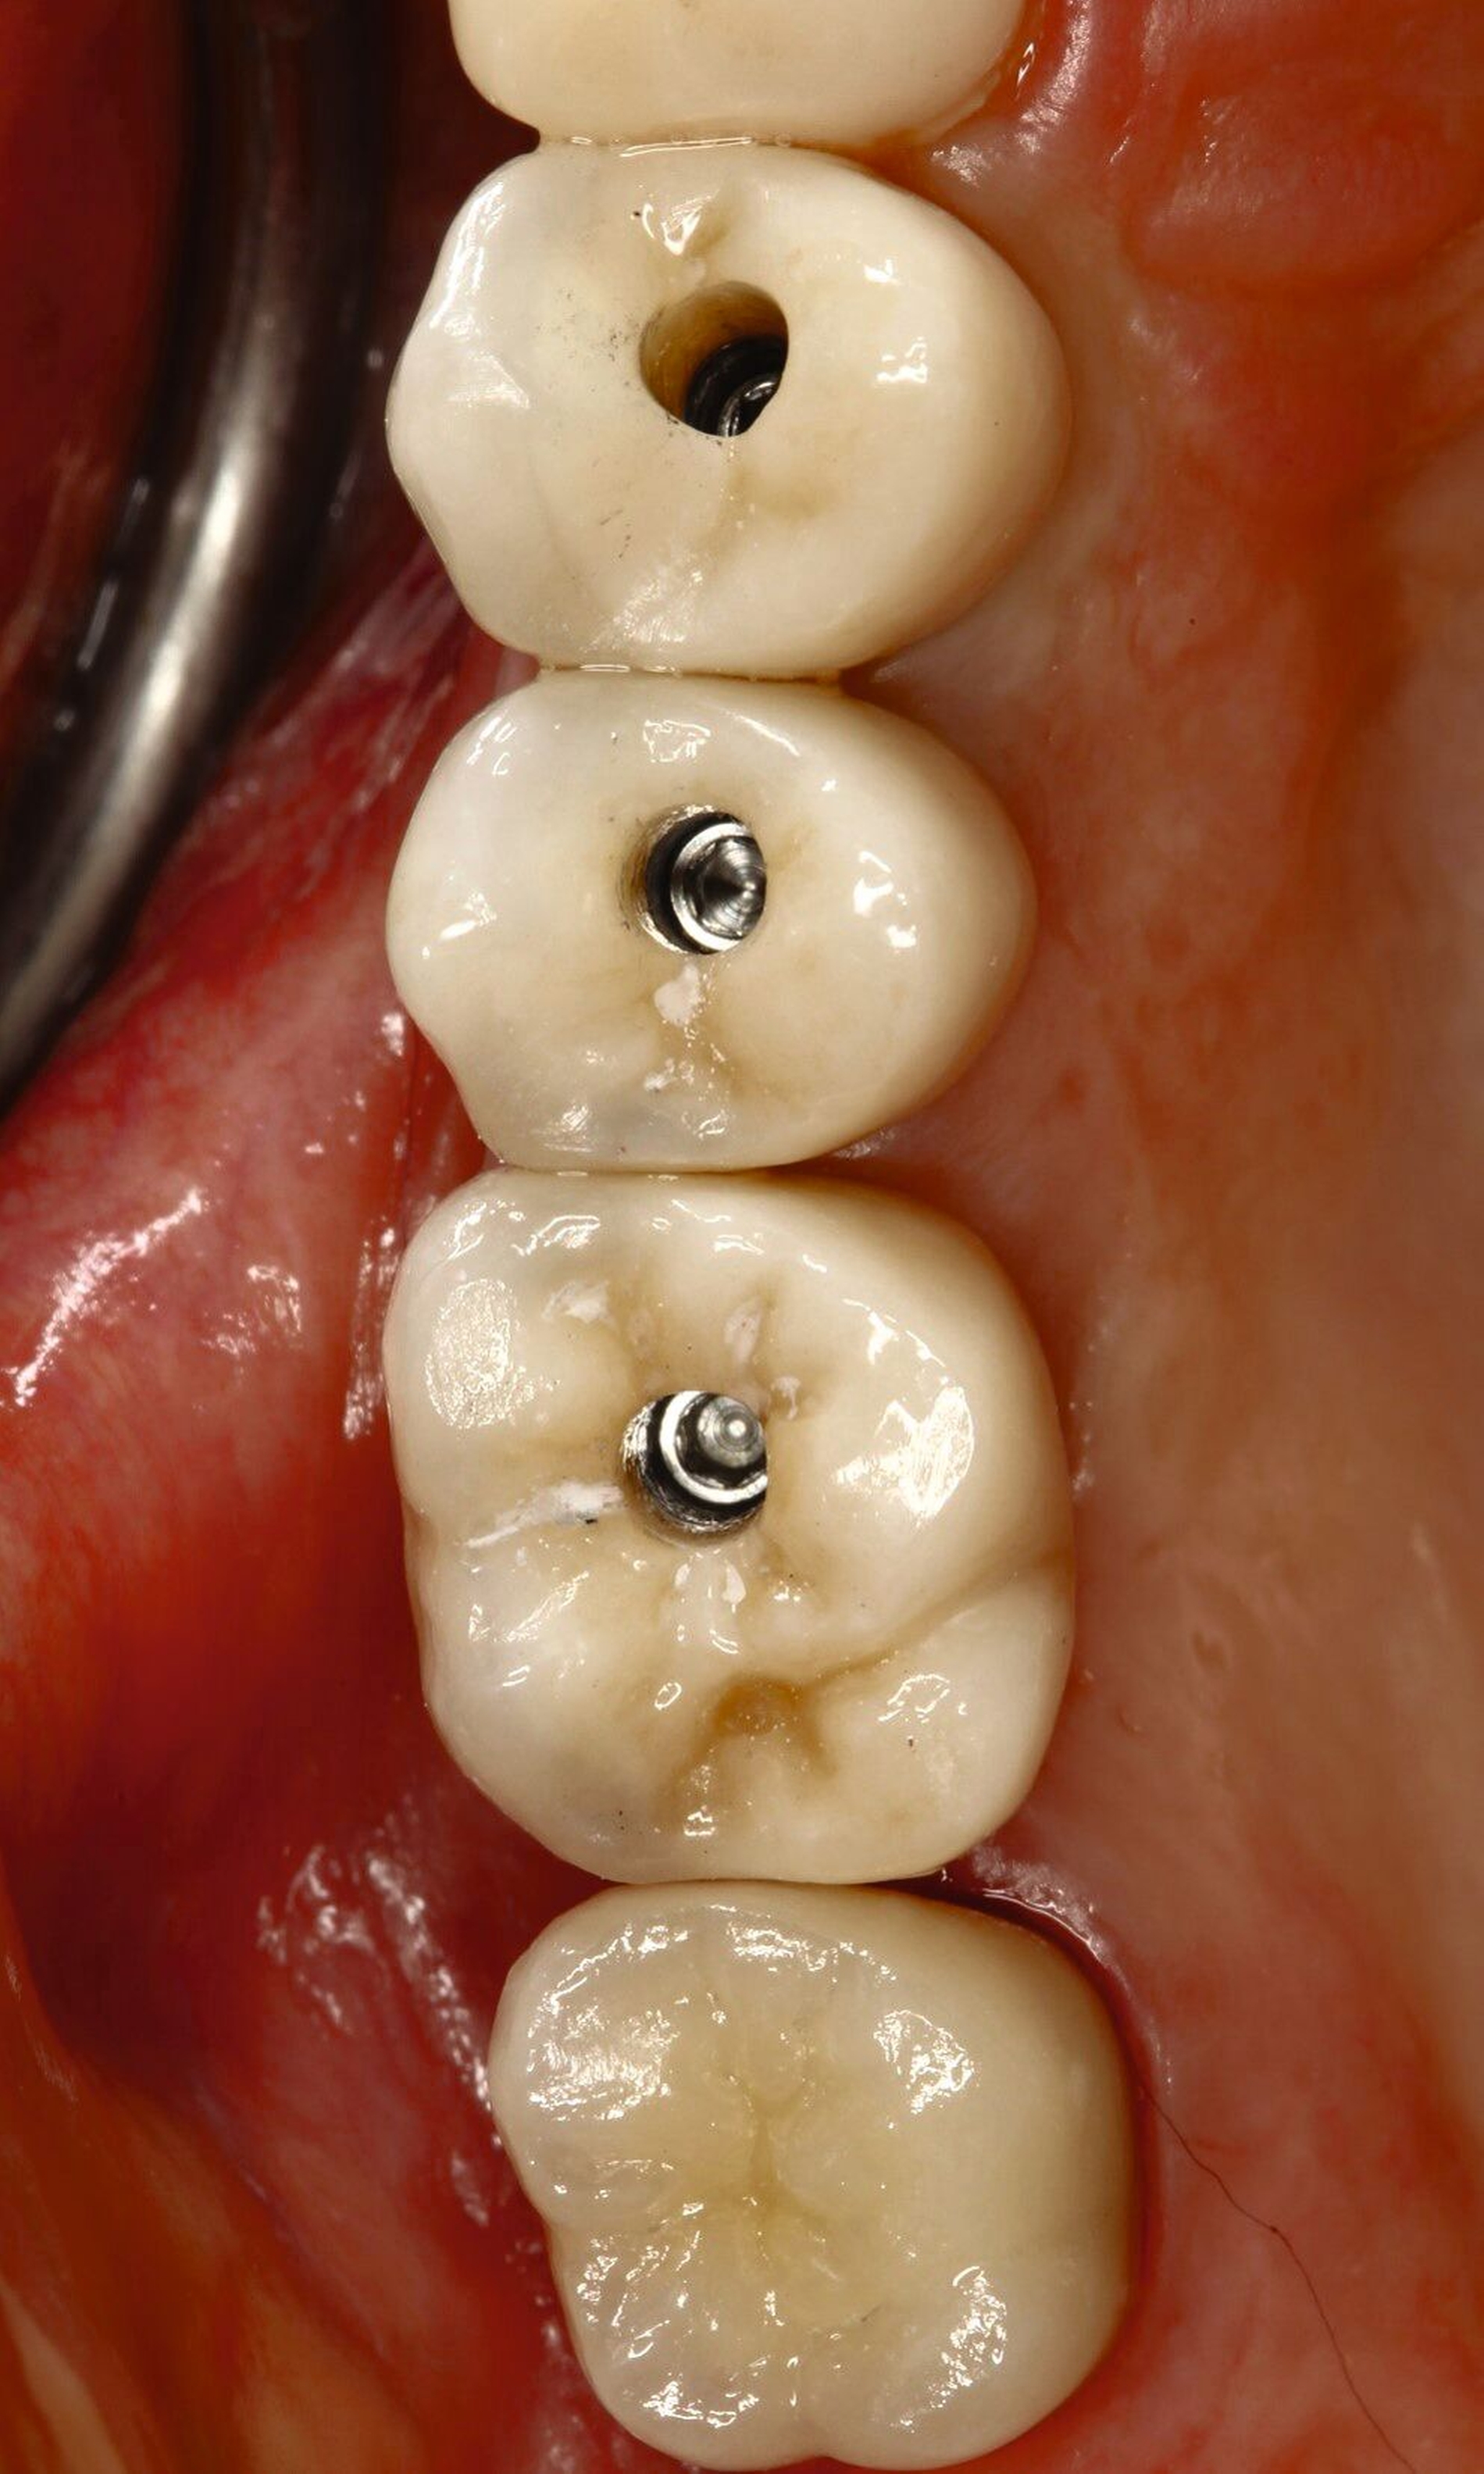

In der vorgestellten Situation wird kein therapeutischer Zahnersatz (Langzeitprovisorium) benötigt, daher bekommt unser Fall das Label S. Kann eine verschraubbare Krone verwendet werden, erhält diese ebenfalls das Prädikat S, die zementierte Restauration wird mit einem höheren Risiko bewertet.

Fall 2 – complex (chirurgisch/prothetisch)

Fall 1: Chirurgie/Prothetik: PD Dr. Stefano Pieralli

Fall 2: Chirurgie: Prof. Dr. Stimmelmayr, Prothetik: Univ.-Prof. Dr. Beuer, MME